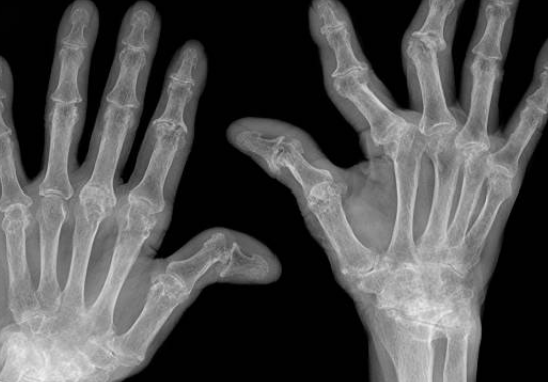

류마티스 관절염은 주로 관절에 영향을 미치는 만성 자가면역 질환으로, 면역 체계가 자신의 신체 조직을 잘못 인식하여 공격하게 되는 상황을 말합니다. 이로 인해 관절과 주변 조직에서 염증이 발생하고, 통증과 부종이 동반됩니다. 이 질환은 주로 손가락, 손목, 무릎 등의 작은 관절에 자주 발생하며, 시간이 지남에 따라 더 큰 관절로도 진행될 수 있습니다. 이러한 염증 반응은 관절의 연골을 파괴하고 결국 골절 및 관절 변형을 초래할 수 있어, 조기 발견 및 적절한 치료가 필수적인 상태입니다.

류마티스 관절염은 초기, 중기 및 후기 단계로 구분될 수 있습니다. 초기 단계에서는 주로 관절 통증과 부종이 나타나며, 무엇보다 조기 진단이 중요합니다. 중기 단계에서는 더 심한 통증과 함께 관절의 손상이 시작되며, 기능적 제한이 발생할 수 있습니다. 후기 단계에는 장기적인 관절 손상이 일어날 수 있으며, 관절 변형이나 일상적인 활동에 큰 영향을 미칠 수 있습니다.